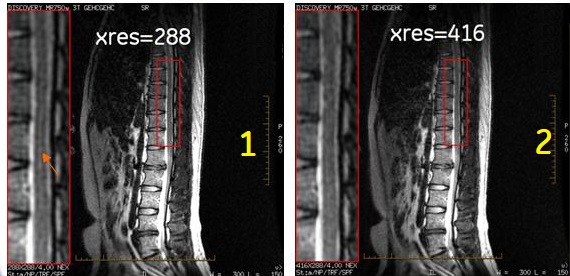

Figure 1. Example of truncation artifact evident in left spine image and resolved on right spine image

Table 1. Image legend

NumberDescription

1

Note: The bright signal/truncation artifact in the spinal column. The image was acquired with the following parameters:

• FOV = 50 cm

• Frequency matrix value = 288

• Phase matrix value = 288

• Frequency direction = Right/Left

• Body coil

• PSD = FSE

• Imaging Options = TRF

• TR = 3000 ms

• TE = 100 ms

• ETL = 16

• Slice thickness = 3 mm

• NEX = 4

• Bandwidth = 31.2 kHz

2

Note: The truncation artifact is no longer present. All scan parameters are the same except the following:

• Frequency matrix value = 416